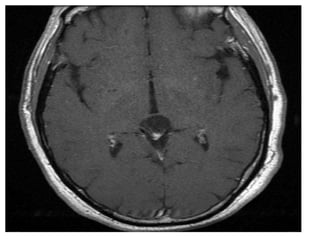

b) Pineoblastoma :

-Highly malignant PNET (Primitive Neuroectodermal

Tumors)

-In patients with trilateral retinoblastoma, Pineoblastoma

may develop in patients with familial and or bilateral

retinoblastoma

-(Exploded calcifications) along outside of mass

(peripherally), unlike germinoma which engulfs and

induces calcification of the pineal gland

-Dense enhancement

-Larger, more heterogeneous with much greater

propensity for local invasion and CNS dissemination

b) Pineoblastoma : -Highlymalignant PNET (Primitive Neuroectodermal Tumors) -In patients with trilateral retinoblastoma, Pineoblastoma may develop in patients with familial and or bilateral retinoblastoma -(Exploded calcifications) along outside of mass (peripherally), unlike germinoma which engulfs and induces calcification of the pineal gland -Dense enhancement -Larger, more heterogeneous with much greater propensity for local invasion and CNS dissemination